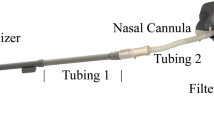

Acoustically driven nebulized drug delivery (acoustic aerosol delivery) is the most efficient noninvasive technique for drug delivery to maxillary sinuses (MS). This method is based on the oscillation of the air plug inside the ostium to transport drug particles from the nasal cavity (NC) to the MS. The larger the wavelength of the air plug oscillation in the ostium, the greater the penetration of drug particles to the MS. However, using this technique, the maximum drug delivery efficiency achieved to date is 5%, which means 95% of the aerosolized drugs do not enter the MS and are wasted. Since the largest amplitude of the air plug oscillation occurs at its resonance frequency, to achieve an improved MS drug delivery efficiency, it is important to determine the resonance frequency of the nose–sinus combination accurately. This paper aims to investigate the impact of geometrical parameters on the resonance frequency of the nose–sinus model. Both experimental and computational acoustic models, along with the theoretical analysis, were conducted to determine the resonance frequency of an idealized nose–sinus model. The computational modeling was carried out using computational fluid dynamics (CFD) and finite element analysis (FEA), whereas in the analytical solution, the mathematical relationships developed for a conventional Helmholtz resonator were employed. A series of experiments were also conducted to measure the resonance frequency of a realistic NC–MS combination. The results demonstrated a good agreement between the experimental and CFD modeling, while the FEA and theoretical analysis showed a significant deviation from the experimental data. Also, it was shown that the resonance frequency of the idealized nose–sinus model increases by up to twofold with increasing the ostium diameter from 3 to 9 mm; however, it has an inverse relationship with the ostium length and sinus volume. It was also reported that the resonance frequency of the nose–sinus model is independent of the NC width and MS shape.

Pourmehran, O., Arjomandi, M., Cazzolato, B. et al. The impact of geometrical parameters on acoustically driven drug delivery to maxillary sinuses. Biomech Model Mechanobiol 19, 557–575 (2020). https://doi.org/10.1007/s10237-019-01230-5